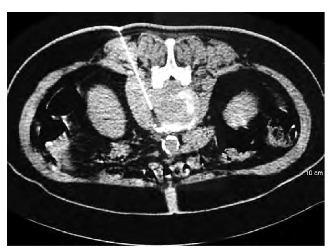

Tomografía computarizada (TC): precisión en zonas complejas

La TC permite obtener imágenes detalladas en múltiples planos, facilitando el acceso a lesiones profundas o cercanas a estructuras vitales. Es especialmente útil en pulmón, abdomen y lesiones óseas.